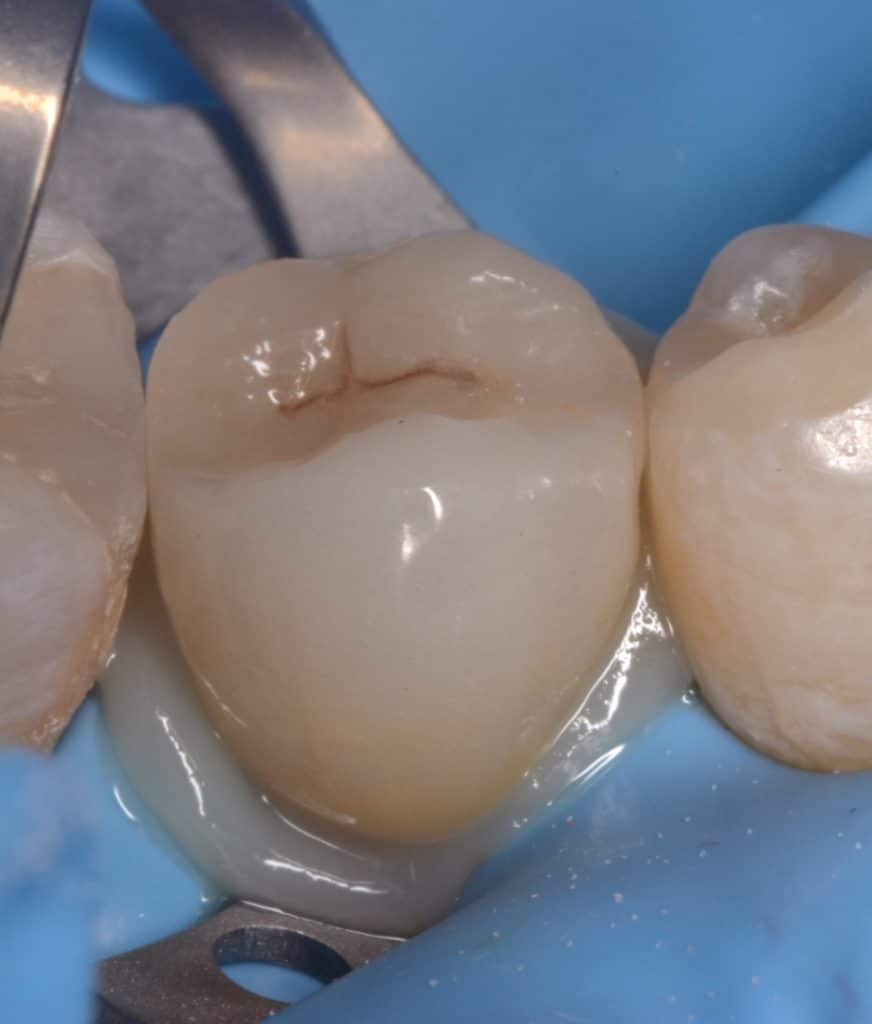

Initial situation showing severe decay in lower second premolar

If you can isolate it you can fix it, isolation with rubberdam

Step by step starting DME